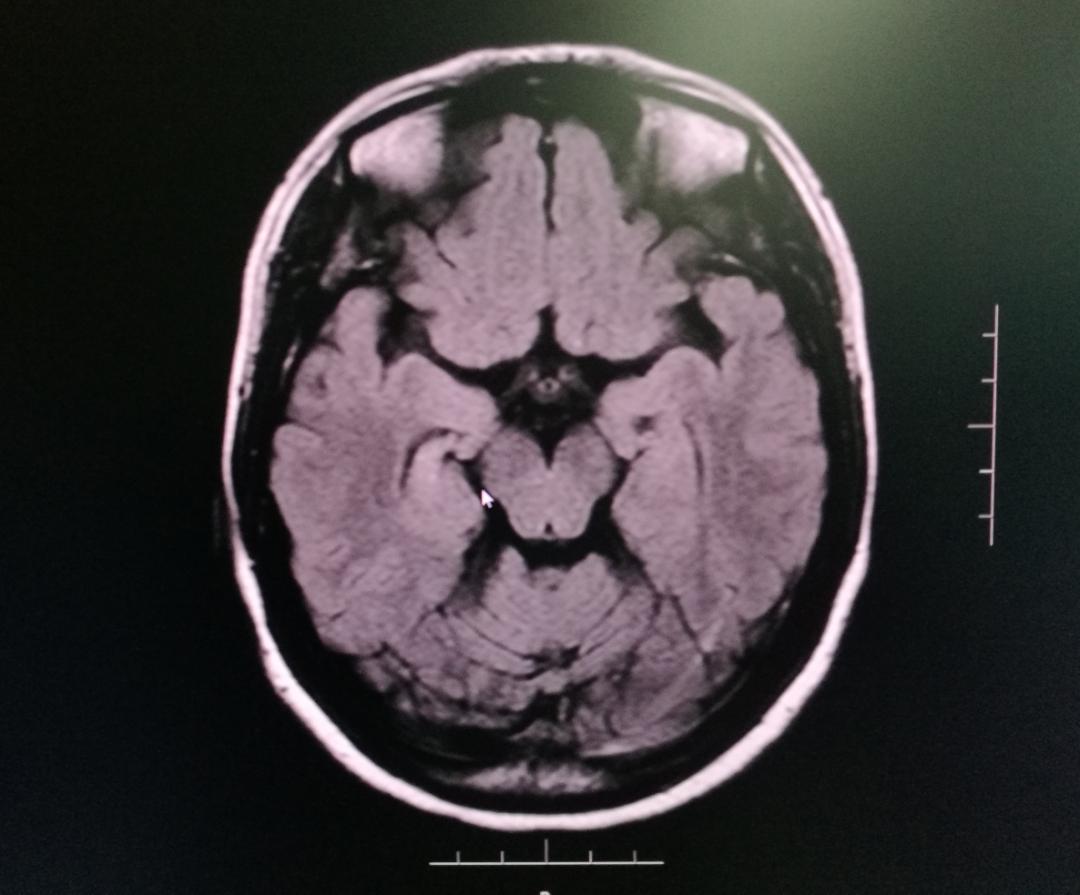

何女士于2012年找到广东三九脑科医院癫痫中心癫痫内科胡湘蜀主任医师。当时我院脑电图检查提示患者右侧前头部异常放电,头颅MRI显示患者右侧海马硬化。经过调整治疗方案,在随后几年里,何女士的癫痫都得到了很好的控制。